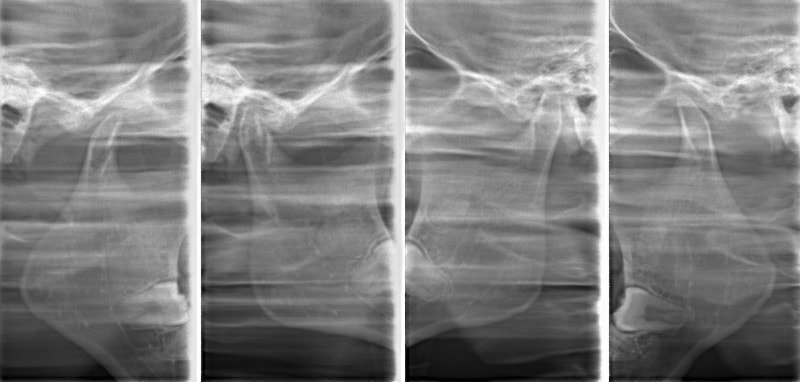

検査時顎関節

非対称のケースによくみられる、顎関節の変形や、CO-CRの不一致、位置の不正が認められます。

治療後の顎関節レントゲン

CO-CRの一致、顎関節位置の改善が認められます。